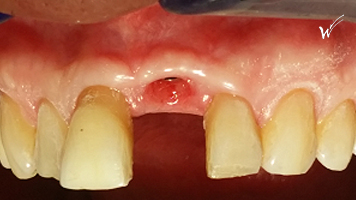

L’implant a été positionné dans l’alvéole, aligné avec la racine. À ce stade, un guide chirurgical peut s’avérer extrêmement utile, en particulier pour éviter d’éventuels obstacles anatomiques, tels que des paquets vasculo-nerveux situés dans le trou rétro-incisif.

Après la guérison des tissus mous (gencive) et durs (os alvéolaire), la couronne céramique esthétique a été installée sur l’implant.

Cicatrisation des tissus et résultat clinique à la pose de la couronne céramique